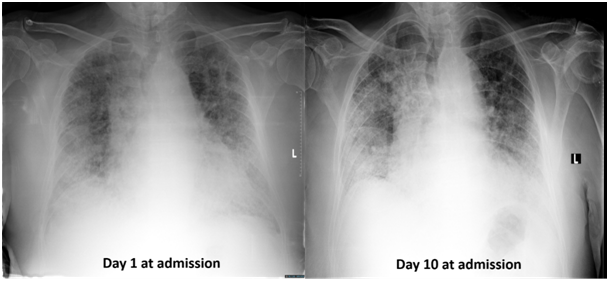

At the second week after completion of radiotherapy, he was emergently attended the pulmonary medicine clinic with rapidly progressive dyspnea and severe respiratory distress. Partial oxygen tension was 77 mmHg under 55% O2, and the chest X-ray revealed newly developing diffuse pulmonary infiltrates. Acute radiation pneumonitis was ruled out due to the fact that diffuse pulmonary infiltration was not matching the irradiated lung volume and radiotherapy entrance tracks; the contralateral right lung was mainly diffusely effected which was receiving insignificant radiotherapy doses (Figure 2). He had no fever or productive cough. The bronchial lavage bacterial and fungal culture findings were negative. Acute cardiac events were excluded with transesophageal echocardiography and electrocardiography. According to these data, the patient was evaluated as acute exacerbation of IPF and he was given prednisolone 160mg per day with meropenem 3x 500mg intravenous. In spite of using intensive medication his medical condition got worse. He was mechanically ventilated because of refractory hypoxia and he died of respiratory arrest on 15th day of the hospitalization.

Radiation pneumonitis (RP) may be thought as the cause of these clinical and radiological symptoms especially due to the chronic damage of lung tissue. There have been few studies about SABR and its pulmonary effects. Radiation induced pneumonitis was reported as the most frequent acute pulmonary toxicity after SABR.13 Guckenberger et al investigated pulmonary injury after SABR and grade 2 and 3 pneumonitis rate was reported as 5.8 % with this study.14 Similarly, Yamaguchi et al. evaluated the association between subclinical interstitial lung disease (ILD) and fatal RP in patients with thoracic tumors treated with thoracic radiotherapy.15 According to this study, subclinical ILD was found as a statistically significant factor influencing the development of RP and fatal RP was reported more common in this group. In addition, extensive fibrosis on pre-treatment CT was regarded as a contraindication for thoracic radiotherapy. In the present case underlying lung disease had an important risk factor for RP. However, occurrence time and localization of lesions were not compatible with acute radiation pneumonitis, as diffuse pulmonary infiltration observed in X-rays were not matching the irradiated lung volume and the contralateral right lung was main site contributing the AE. Radiation related consolidation areas of pneumonitis needs to be within and adjacent to the radiation port;16,17 moreover, the timing of AE in our case is not fitting the usual RP generally developing between 3 to 5months after completion of radiotherapy. In particular, if patients with underlying pre-existing IPF develop RP after SABR, in majority of the patients radiologic changes in lung tissue do not arise before 3months after SABR and clinical symptoms of RP usually occur between 3 to 6months after SABR.18 Obviously, although RP was the main differential diagnosis for our case, the onset of the clinical and radiologic symptoms was not compatible with this.